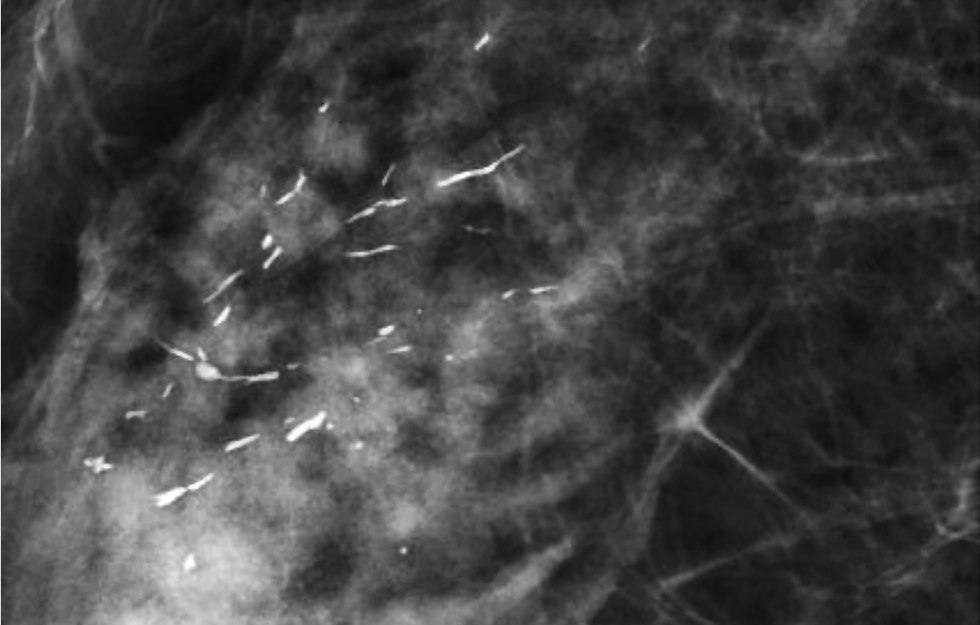

Множественные рассеянные точечные микрокальцинаты характерны для склерозирующего аденоза – доброкачественного состояния, при котором отмечается увеличение долек молочных желез и их дисторция окружающей фиброзной тканью [13] (Рис.7).